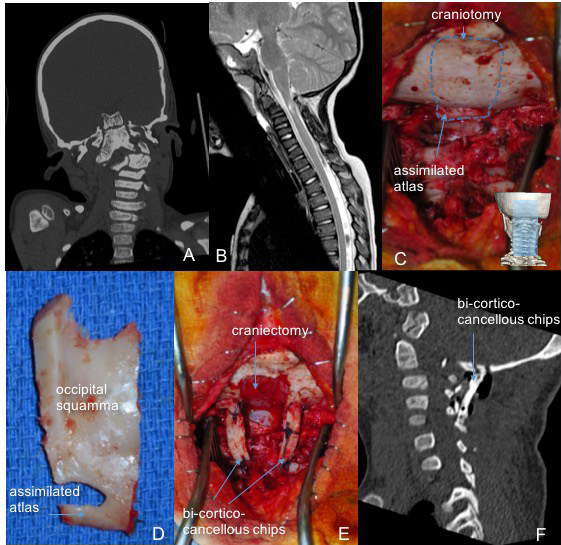

dysplasie de charnière complexe révélée par tétraparésie régressive, 4 ans ; décompression-greffe autologue sans matériel d’ostéosynthèse et immobilisation par minerve

A-C : os odontoideum dans un syndrome de Borjeson-Forsman-Lehman ; D : réduction par traction axiale par étrier de Gardner et fixation en rétropulsion par tiges-plaques et autogreffe d’os occipital (E, F)